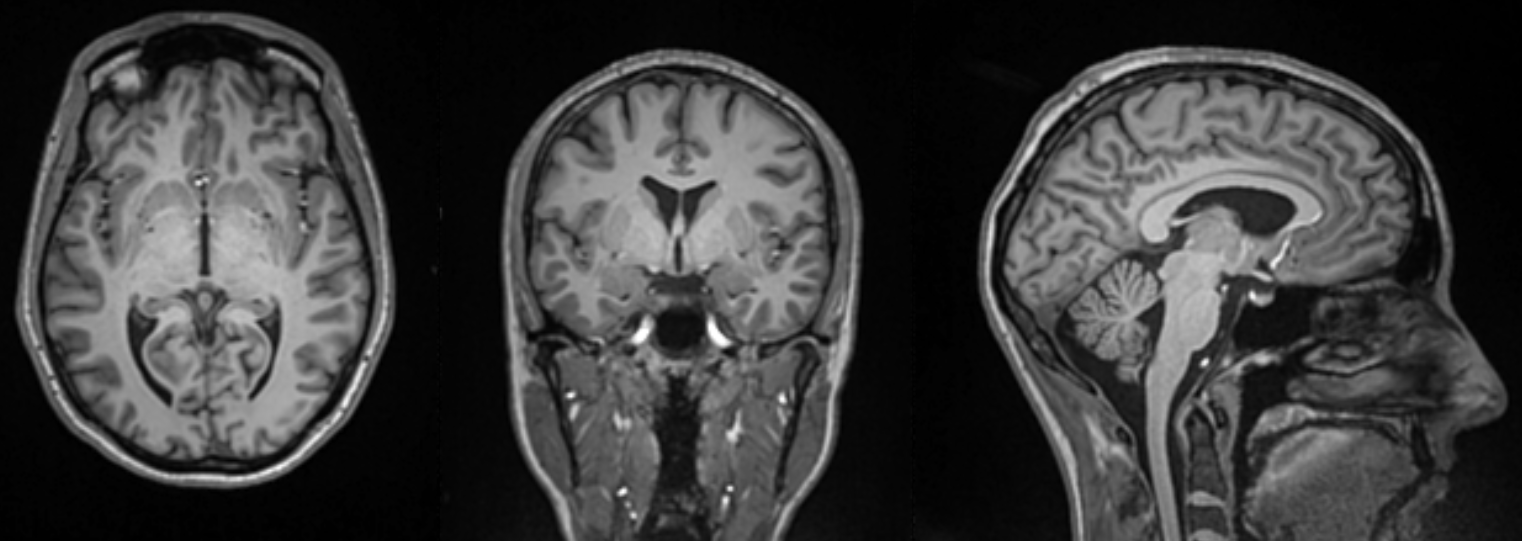

“We use functional MRI, structural MRI and diffusion MRI to observe changes in brain structure, connectivity and activity when individuals engage in various cognitive and hearing tasks,” MacPhee explains.

What they’ve found is an individual’s hearing capacity can affect the brain’s anatomy. One change observed is the thickness of the cerebral cortex – the outer layer of the brain responsible for higher cognitive functions. Cortical thickness has proven to be a biomarker used to predict the progression of dementia.

Some of MacPhee’s tests also include stimulation exercises, where subjects listen to certain sounds while their brain activity is monitored in central areas – such as the auditory cortex which is responsible for processing sound.

“By observing the brain’s response to these stimuli, we can map out the regions of the brain that are involved in auditory processing and how they are affected by hearing loss,” MacPhee says.